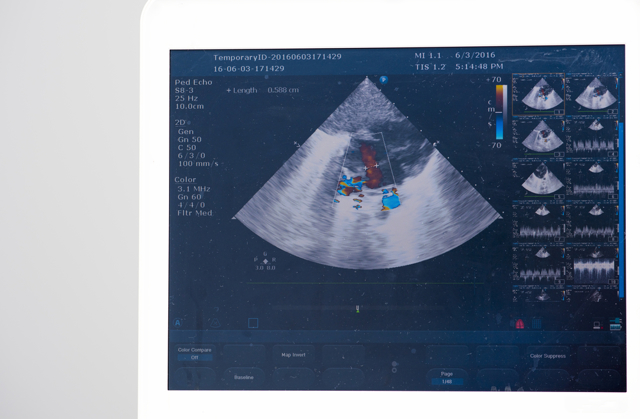

- Датчик, установленный на голове, посылает ультразвуковой сигнал, который доходит до объекта исследования (артерий, вен), отражается от него, и полученный сигнал выводится на специальный монитор.

- Причем картинка, которая получается в результате совершенно непохожа на рисунок кровеносной системы, к которому так все привыкли.

- Врач работает с показателями в итоговом виде – изображениями, графиками, схемами.

Датчик фиксирует отраженные волны и передает сигнал компьютеру, где формируется целостная картина во время исследования.

Искажение отражения ультразвука от движущихся объектов описывает эффект Допплера. Сосуды с остановленным кровотоком не дают такого эффекта.

Для наглядности, полученное изображение кровотока на мониторе окрашивается в два цвета — синий и красный. Оттенок меняется в зависимости от аномальных волн, повышения или понижения давления в сосуде и других изменений.